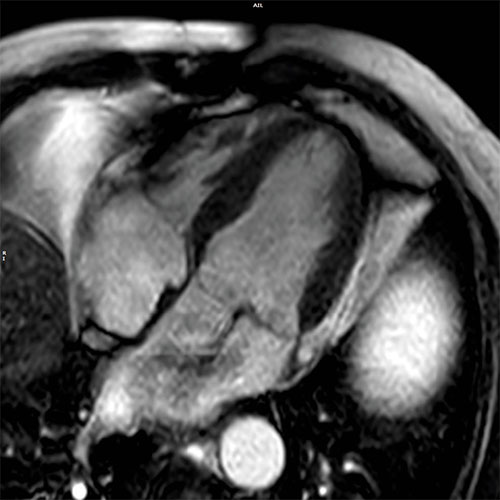

Cardiac MR images of a patient with non-ischemic cardiomyopathy showing delayed enhancement and severe mitral regurgitation.

PSIR - 4 chamber view

bTFE - 4 chamber view

EPI cine - 4 chamber view